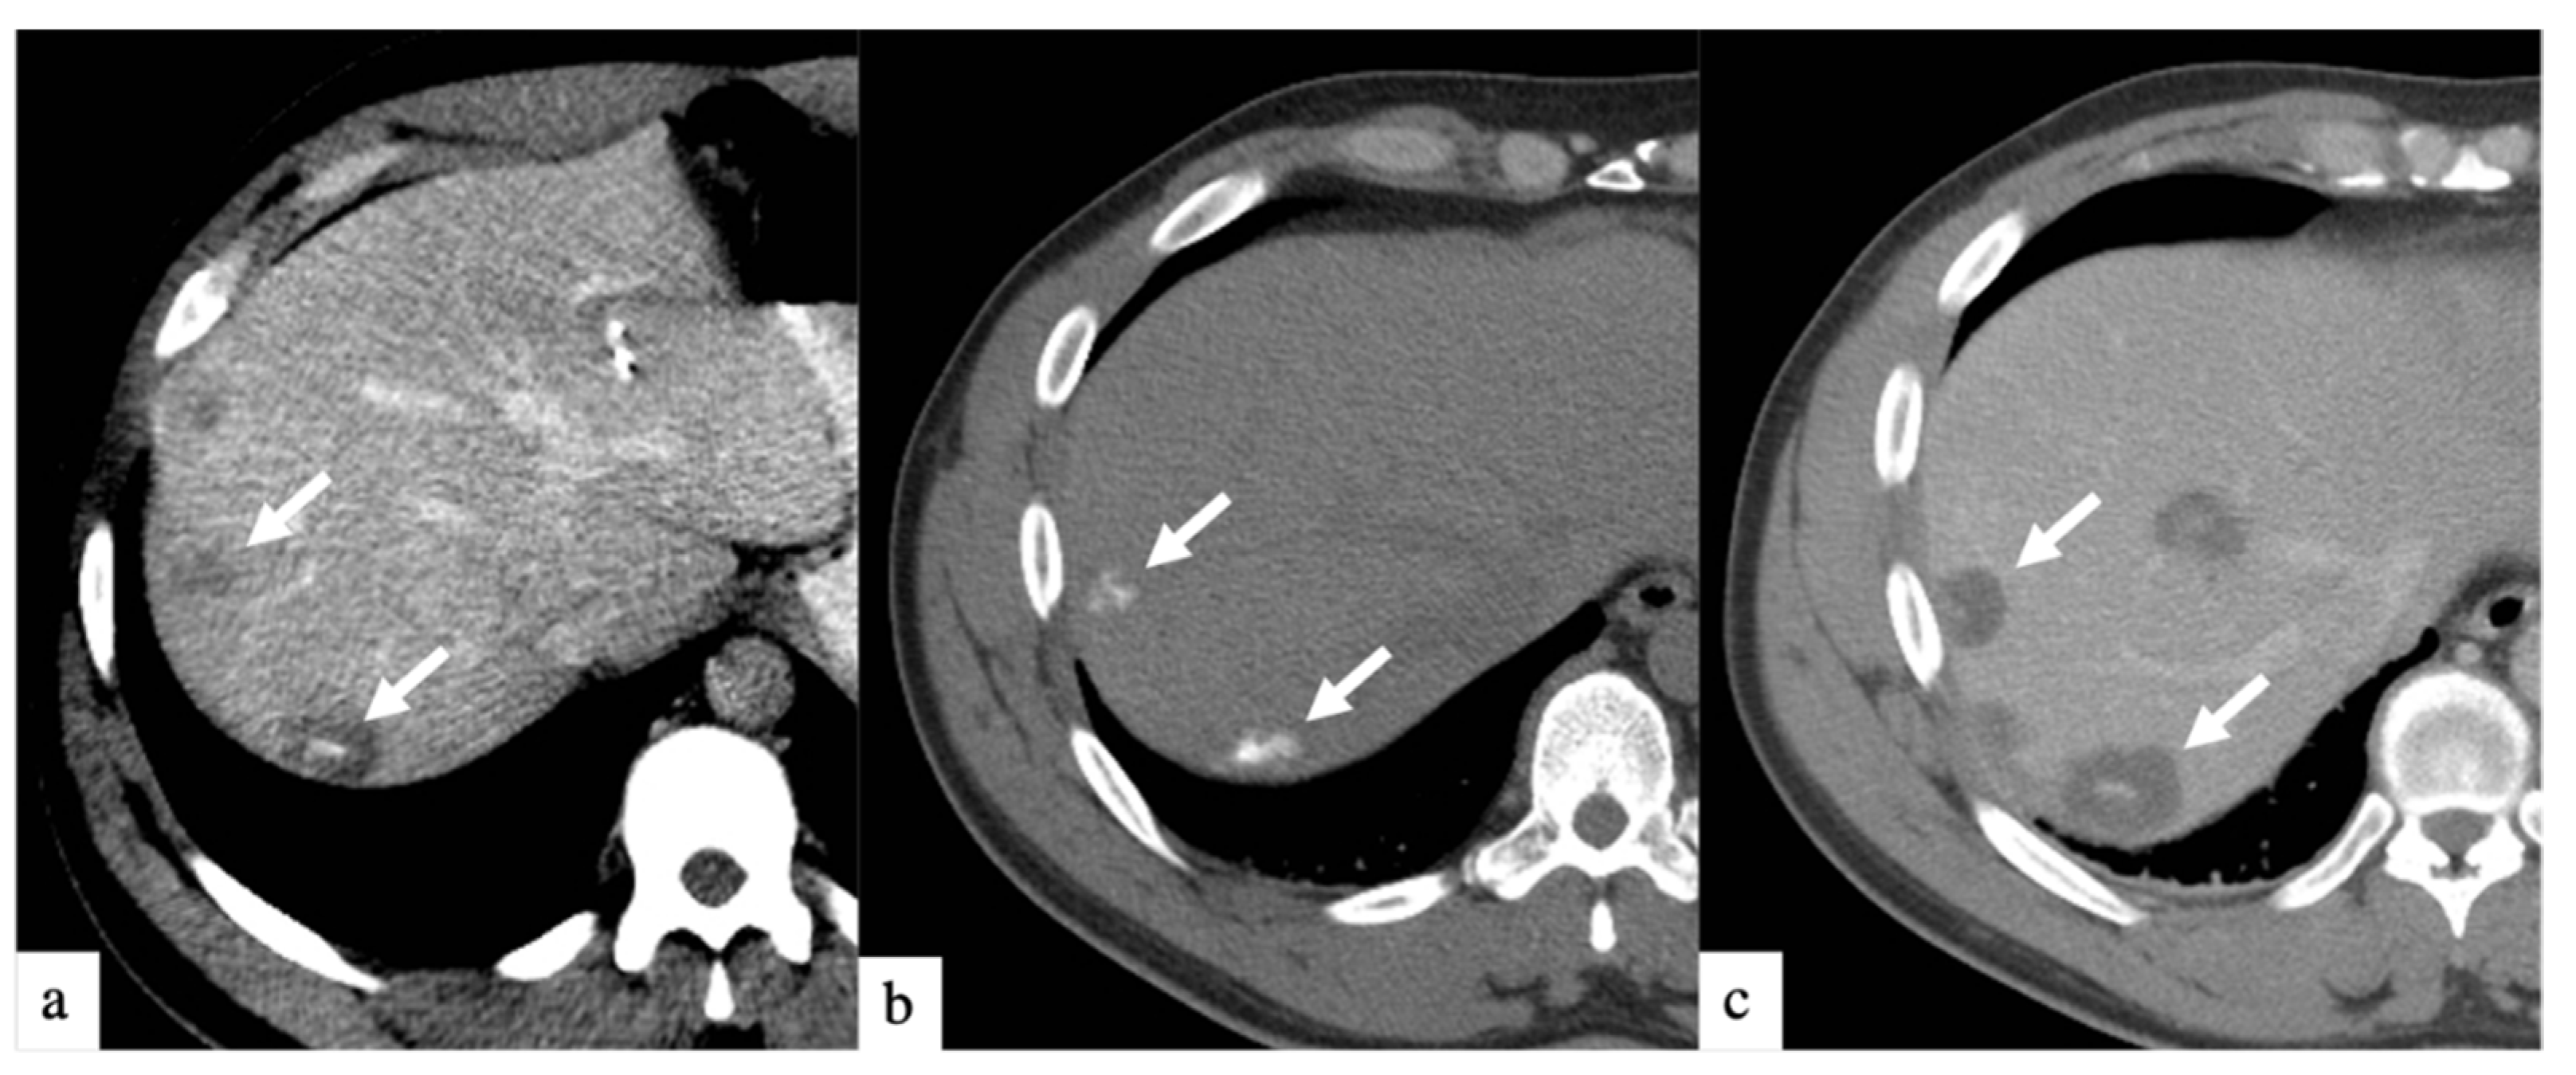

DEBIRI therapy is known to be safe in patients receiving concurrent systemic chemotherapy [18]. Although prior randomized controlled trials [12,13] and prospective studies [19,20] have shown the safety of treatment with larger beads, few studies have reported the safety profile of smaller beads [14,16]. Smaller bead size has the potential of delivering higher drug concentrations distally into the tumor bed, as depicted in Figure 2 and Figure 3. This retrospective study is, to our knowledge, the largest study evaluating the safety and efficacy of 40 and 75 µm calibrated drug-eluting beads in the treatment of metastatic CRC.

Figure 2.

Axial CT images of a patient with history of colorectal cancer who underwent a single small particle DEBIRI TACE session of right lobe. Portal venous phase CT obtained pre-treatment (a) shows multifocal liver metastases (arrows); non-enhanced CT obtained 1 h post-treatment (b) shows intra-tumoral staining of iodinated contrast trapped by the 40 µm calibrated drug-eluting beads; one-month follow up imaging (c) shows increased areas of low attenuation in keeping with devascularization of tumors (arrows). Patient did not undergo a second DEBIRI due to lowering CEA and evidence of response on imaging. One-year follow-up (material not intended for publication) revealed tumoral progression, patient is being considered for second DEBIRI TACE or TARE at time of publication. Note: although not shown, all lesions seen in (c) were present on (a) and treated.